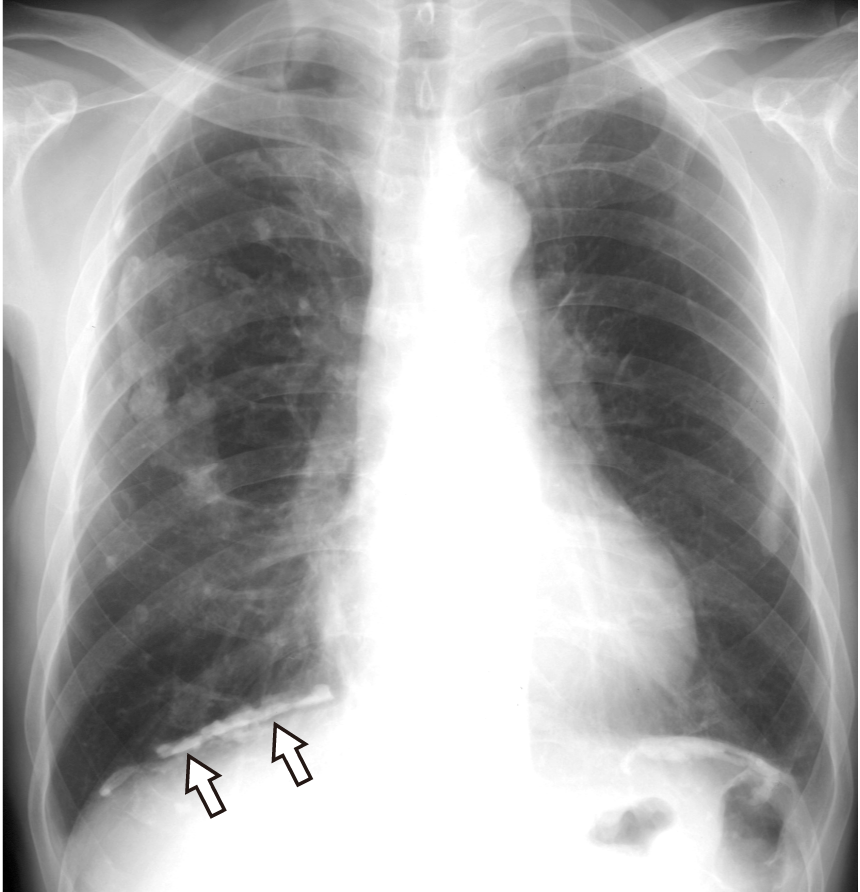

石灰化胸膜プラークの典型画像

横隔胸膜に石灰化胸膜プラークを認め(矢印)、右中野には“柊の葉の石灰化”と称される胸膜プラークを認める。肋骨横隔膜角は正常で鈍化はない。